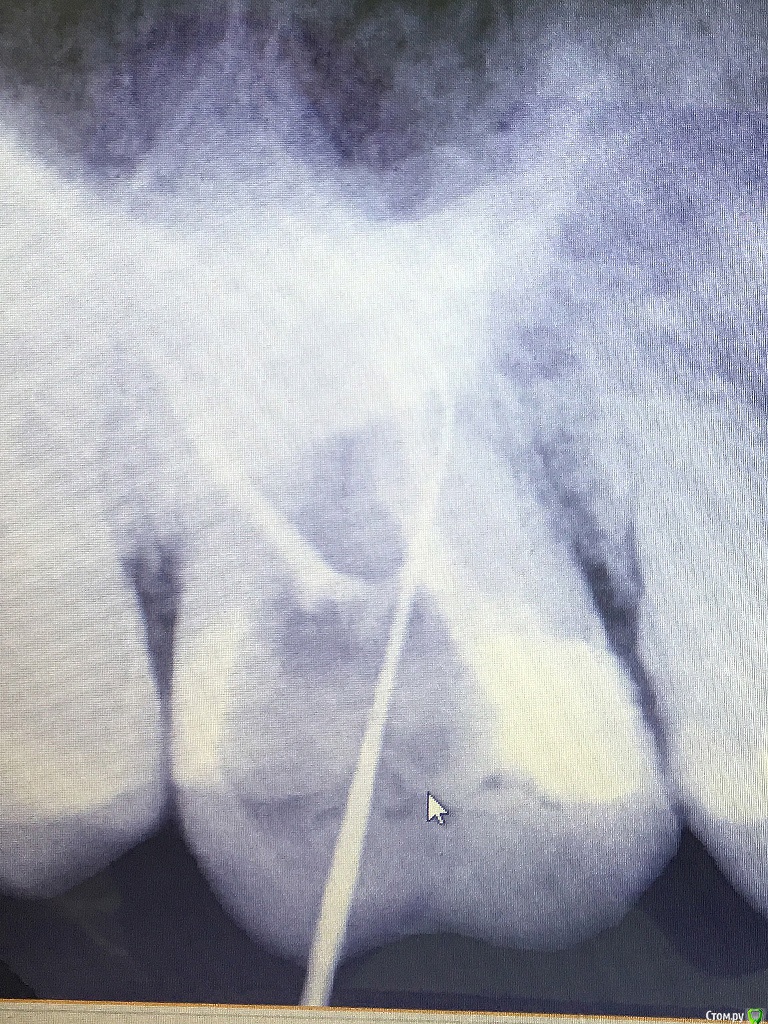

rozmari Опубликовано 20 марта, 2017 Поделиться Опубликовано 20 марта, 2017 Здравствуйте люди добрые.), пытаюсь пролечить верхнюю 7-ку с 14 октября (5 месяцев).Коротко о наболевшем:1. 10 октября выпала пломба, 14 октября пролечил кариес.После лечения зуб ныл после еды, ждали с врачом 1.5 месяца, но боли не прошли.2. 2 декабря положили лекарство, 16 декабря депульпировали зуб, прочистили 3 канала. Далее болей и нытья после еды нет, но не проходит чувствительность зуба, даже на легкое постукивание ногтем с любой стороны, так же неприятно реагирует на зубную щетку....ждемс3. 27 февраля симптомы не проходят, врач говорит пропить 3 дня Найс, пропито, ничего не изменилось. меняю клинику... 4. 9 марта делаю снимок №1 обнаруживаем не долеченный нёбный канал, чистим, ставим временную пломбу 5. 19 марта симптомы не изменились, 2 часа пытаемся прочистить оставшиеся 2 канала (безуспешно), зато с большими сомнениями, но вроде как нашли 4й канал(снимок №3), чистим и ставим временную пломбу. продолжение следует.....на приём через неделю п.с. вижу что качество снимков оставляет желать лучшее, но всё же буду очень благодарен любому совету. Ссылка на комментарий